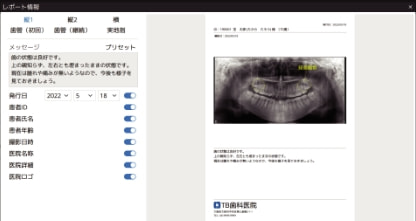

レポート作成機能

患者さんへの説明資料や、保険診療の提供文書の作成ができます。

患者情報や撮影情報、医院情報またメッセージの配置も可能です。

メッセージはあらかじめ登録したプリセットから入力することもできます。